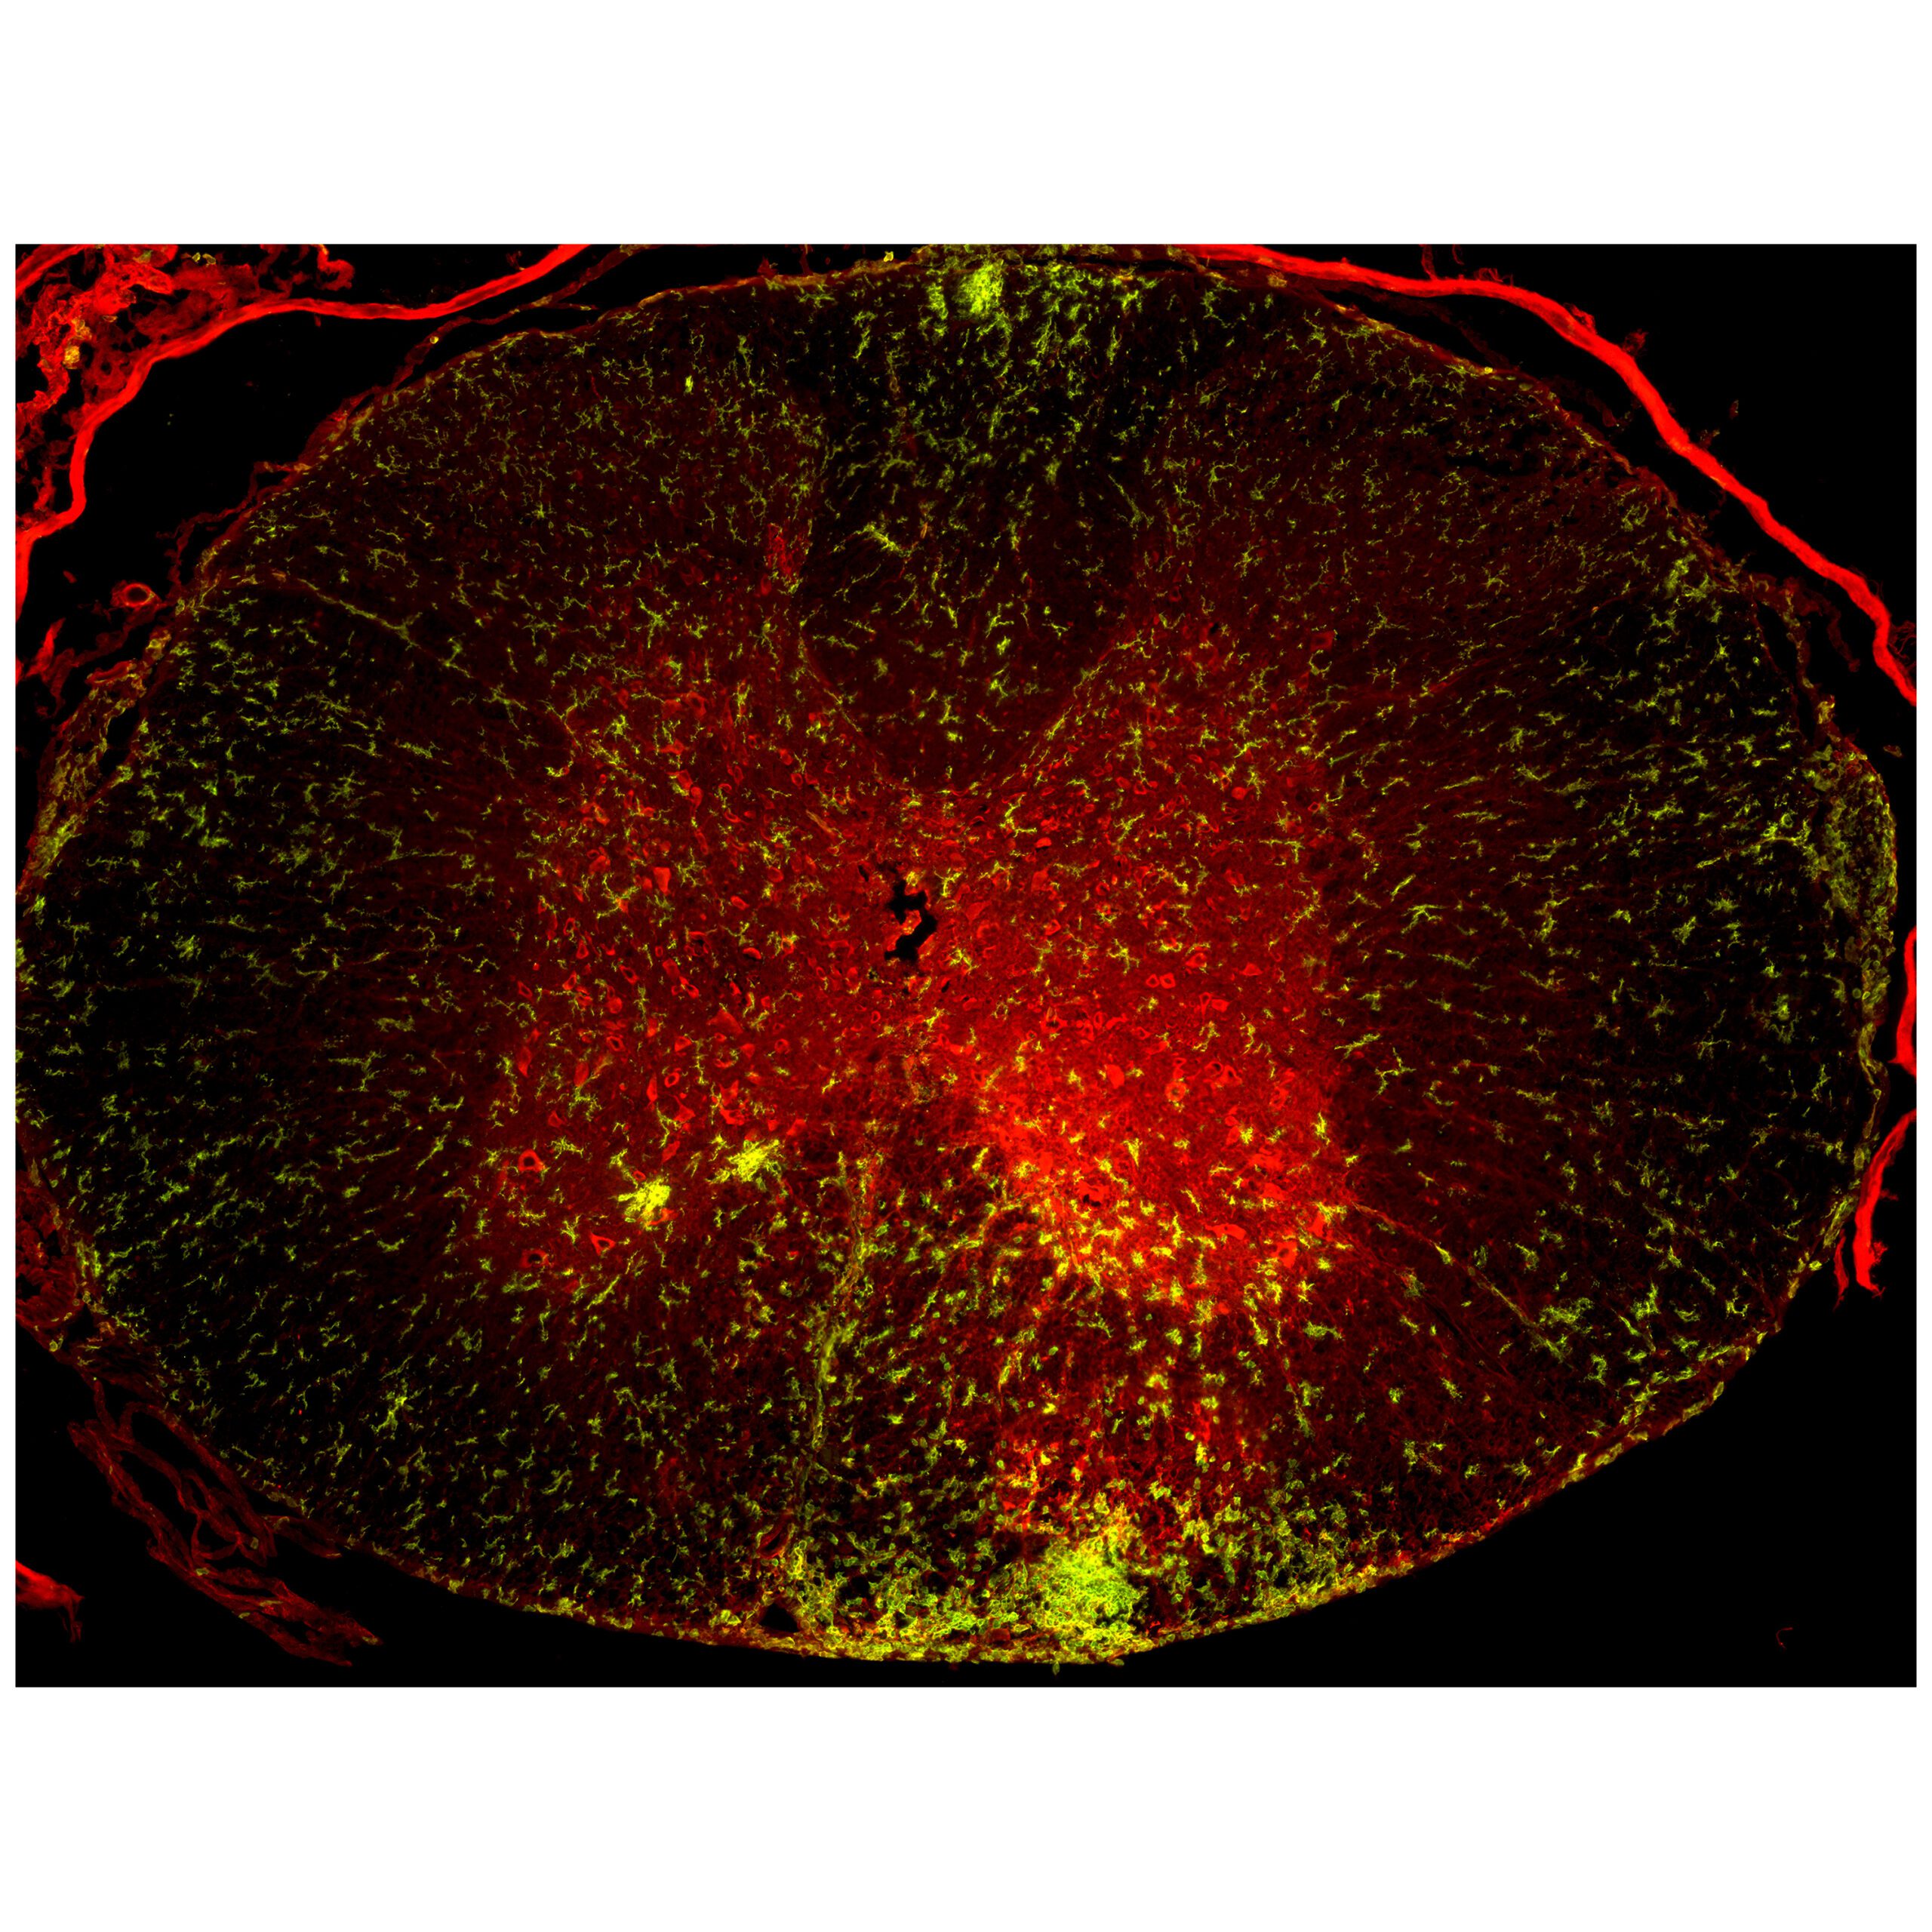

The Miami Project therapeutic pipeline is helping to move new discoveries to the clinic with treatment interventions targeting the acute, subacute and chronic phases of injury. Significant progress is being made in the area of acute care where the cellular and molecular mechanisms underlying neuroprotective interventions such as therapeutic hypothermia are being clarified to enhance our human trials.